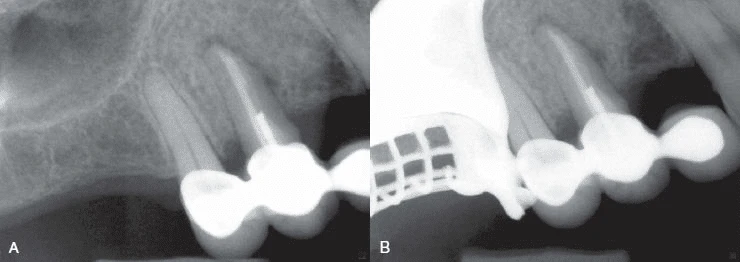

Hình 9. Đôi khi không có dấu hiệu rõ ràng cho thấy lý do răng có triệu chứng. (A) Hình ảnh X quang cho thấy răng cối lớn thứ hai hàm dưới có miếng trám sâu mức độ trung bình. (B) Thử tuỷ cho thấy răng chết tuỷ. Không chiếu sáng nên không thấy có đường nứt nào cả. (C) Chiếu ánh sáng có cường độ cao lên bề mặt răng, quan sát thấy vết nứt ở mặt ngoài. (D) Chiếu sáng vào mặt xa – trong của răng.

ĐÁNH GIÁ X QUANG CỦA NỨT DỌC CHÂN RĂNG

Đôi lúc nứt dọc chân răng hoặc chia chân răng có thể chẩn đoán rõ ràng bằng X quang. Tuy nhiên, hầu hết trường hợp đường nứt nằm trên một mặt phẳng và không nhận ra được trên X quang. Trong một nghiên cứu ở những răng đã được nhổ, các nhà nghiên cứu cho rằng sẽ thấy được vết nứt khi tia X được chiếu trong vòng 4 độ đối với mặt phẳng nứt. Nếu nằm ngoài góc này thì không thấy rõ được đường nứt. Họ cũng nhận thấy rằng nếu có nứt dọc thì chúng chỉ thấy được trên X quang trong 35.7% trường hợp.